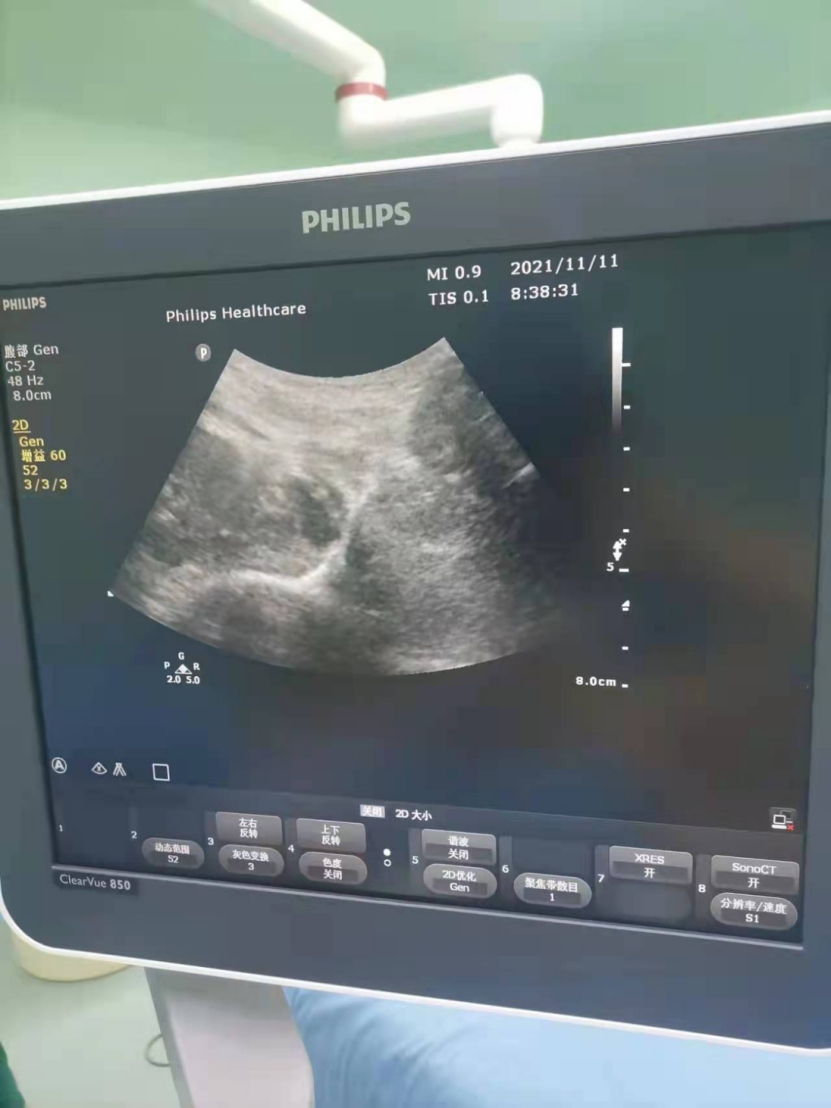

李彦廷医师使用超声为患者行腰丛及骶丛神经阻滞

术野正中暗色区域为注药区